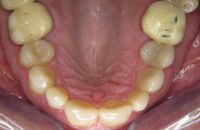

Voor de behandeling

Gebitsslijtage voornamelijk door knarsen. Aan de binnenkant zijn de tanden erg dun geworden en daardoor ook afgebroken. Door de diepe beet zijn de kiezen in onderkaak helemaal afgebroken.